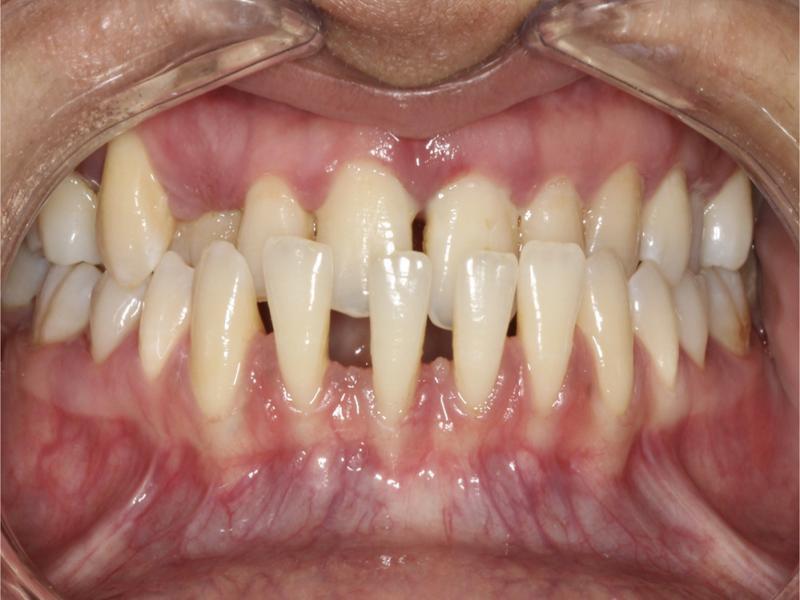

Figure 1.